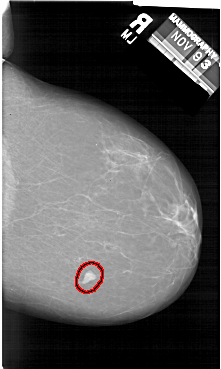

A_1412_1.LEFT_MLO

LEFT_MLO LINES 6511 PIXELS_PER_LINE 4246 BITS_PER_PIXEL 12 RESOLUTION 43.5 NON_OVERLAY

FILE: A_1412_1.RIGHT_MLO.OVERLAY

TOTAL_ABNORMALITIES 1

ABNORMALITY 1

LESION_TYPE MASS SHAPE IRREGULAR MARGINS CIRCUMSCRIBED

ASSESSMENT 4

SUBTLETY 5

PATHOLOGY BENIGN

TOTAL_OUTLINES 1

BOUNDARY